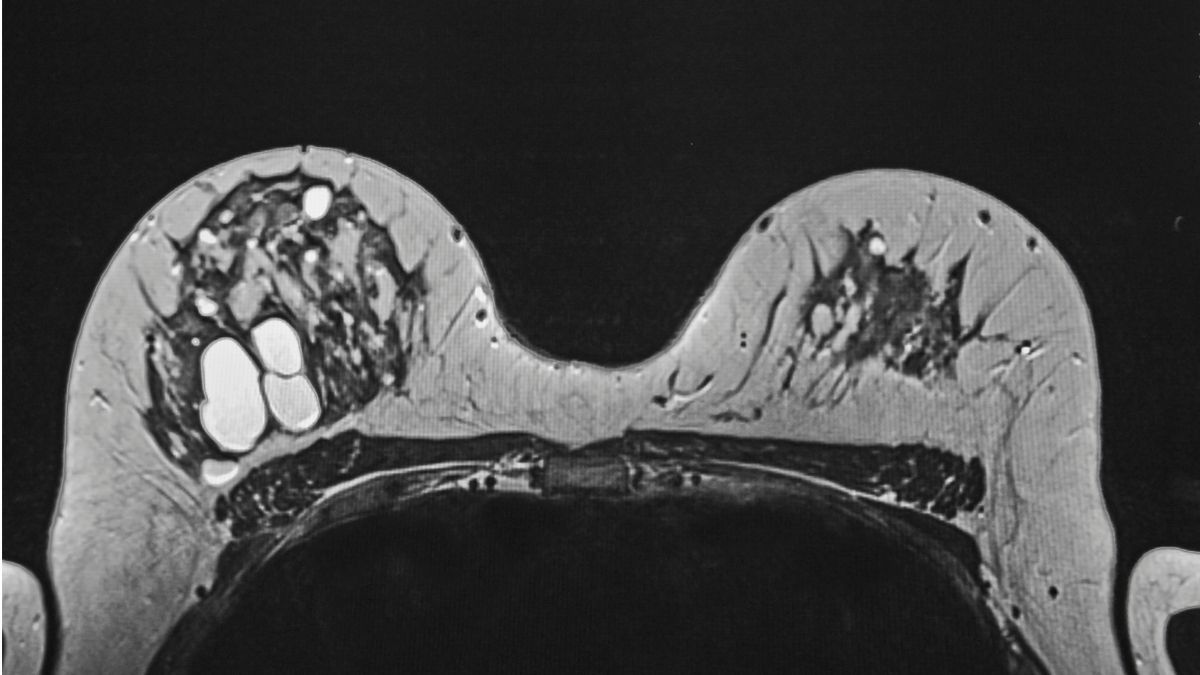

5. Tidak Selalu Akurat Mendeteksi Kanker

Benjolan kanker payudara tidak melulu muncul di bagian yang terpapar sinar-X pada pemeriksaan mamografi. Faktanya, benjolan tersebut juga bisa muncul di area yang tidak terjangkau sinar-X, seperti ketiak.

Mengutip Mayoclinic, pemeriksaan mamografi mungkin akan memberikan hasil yang tidak akurat pada 1 dari 5 wanita dengan kanker payudara.